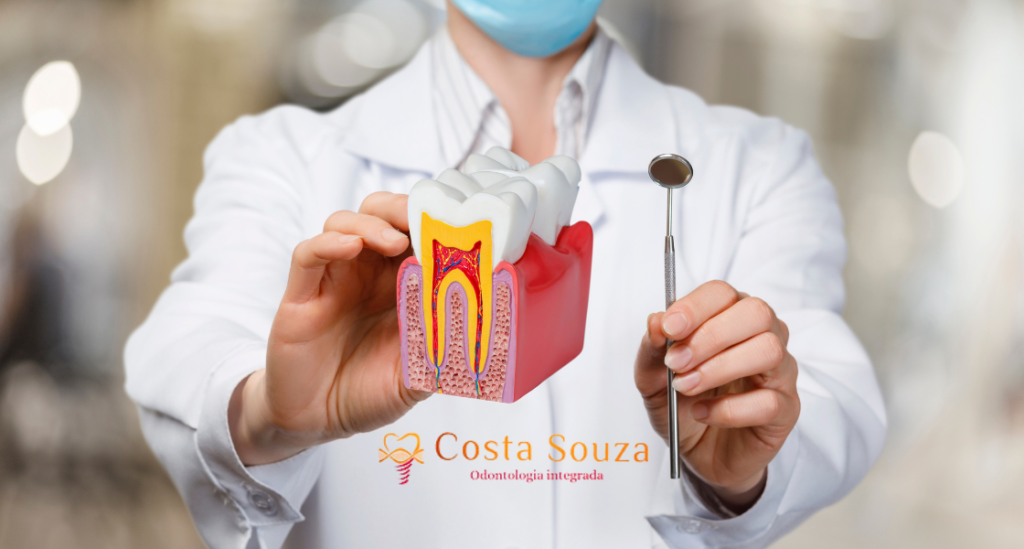

O Tratamento Dentário de Canal é realizado quando a polpa do dente está inflamada ou infectada, geralmente devido a cáries profundas, trauma ou infiltração bacteriana. Durante o procedimento, removemos cuidadosamente a polpa afetada, limpamos e desinfetamos o canal e, em seguida, preenchemos o espaço vazio com um material selante. O objetivo é salvar o dente, aliviar a dor e restaurar sua função normal.